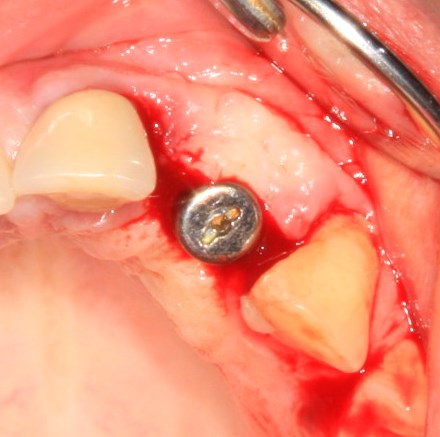

Делаем разрез, скелетируем костную ткань:

Как видите, коллагеновая мембрана полностью резорбировалась, а костный блок прижился и интегрировался на челюстной кости. Можно убрать винты:

и приступить к подготовке лунки под имплантат: